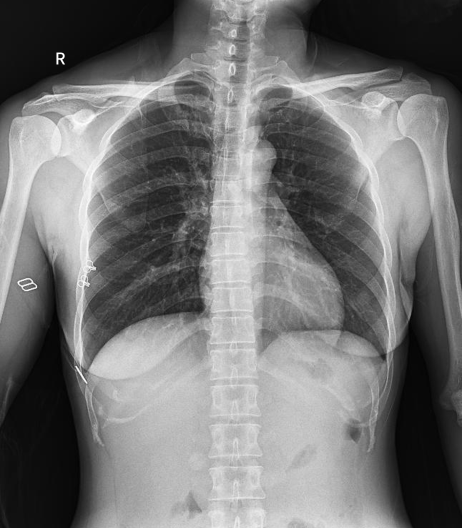

球管傾斜攝影角度-45°~45°,滿足臨床各部位各角度的攝影需求。如:髕骨軸位、頸椎正位、骶尾椎、鼻竇瓦氏位、梅氏位等部位檢查。

拉伸自如:SID電動(dòng)拉伸,最長(zhǎng)可延伸至1.8米,滿足放射科室各種拍片距離的需求。如:GBZ 70-2015職業(yè)性塵肺病的診斷標(biāo)準(zhǔn)中對(duì)胸片拍片距離1.8米的要求。